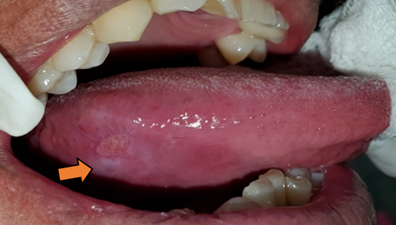

Paciente retorna después de 7 días, para valorar la evolución de la úlcera traumática, misma que reduce de tamaño a 5 x 3 mm, la tumefacción desaparece y es asintomática. Las áreas de queratosis friccional que rodeaban a la úlcera todavía persistían (Figura 5).

Figura 5. Paciente a los 7 días de evolución. Úlcera en proceso de reparación y ausencia de dolor. Queratosis friccional persiste (Flecha naranja).